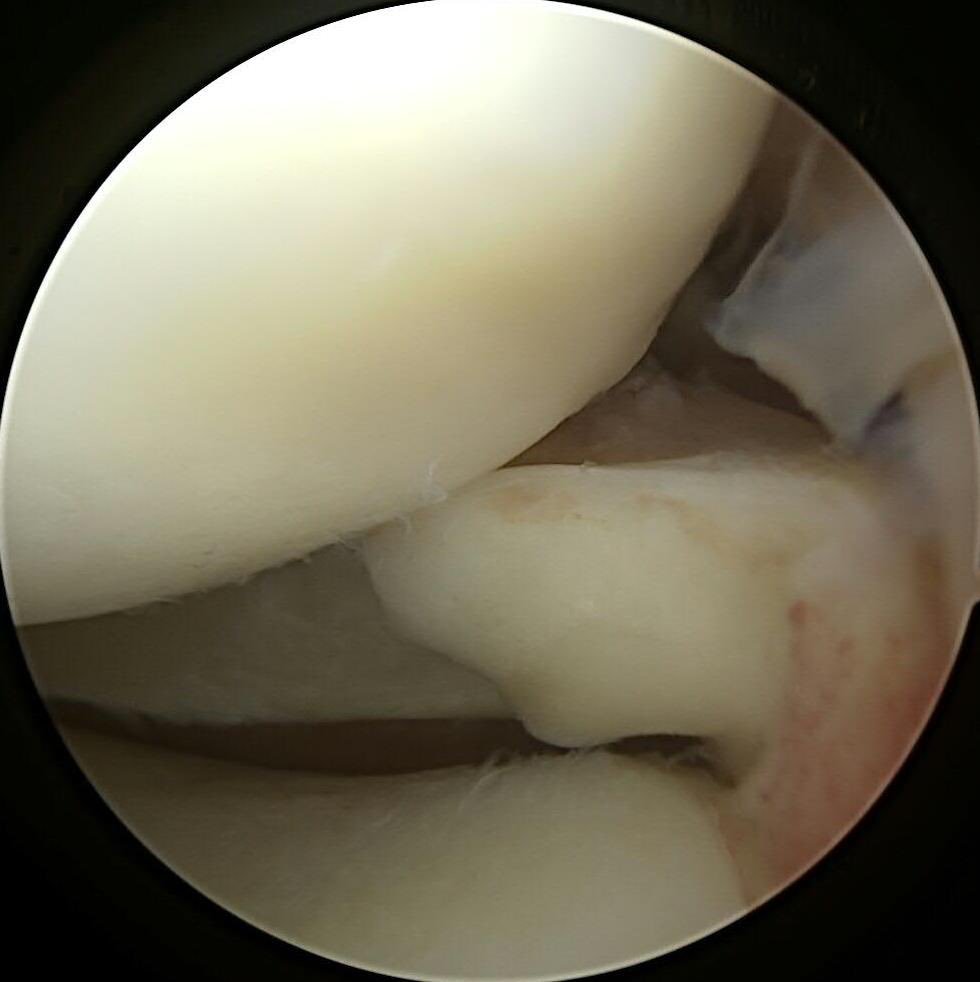

#savethemeniscus LMORT: Lateral Meniscus Oblique Radial Tear- often seen with an acute ACL injury. REPAIR or RESECT?